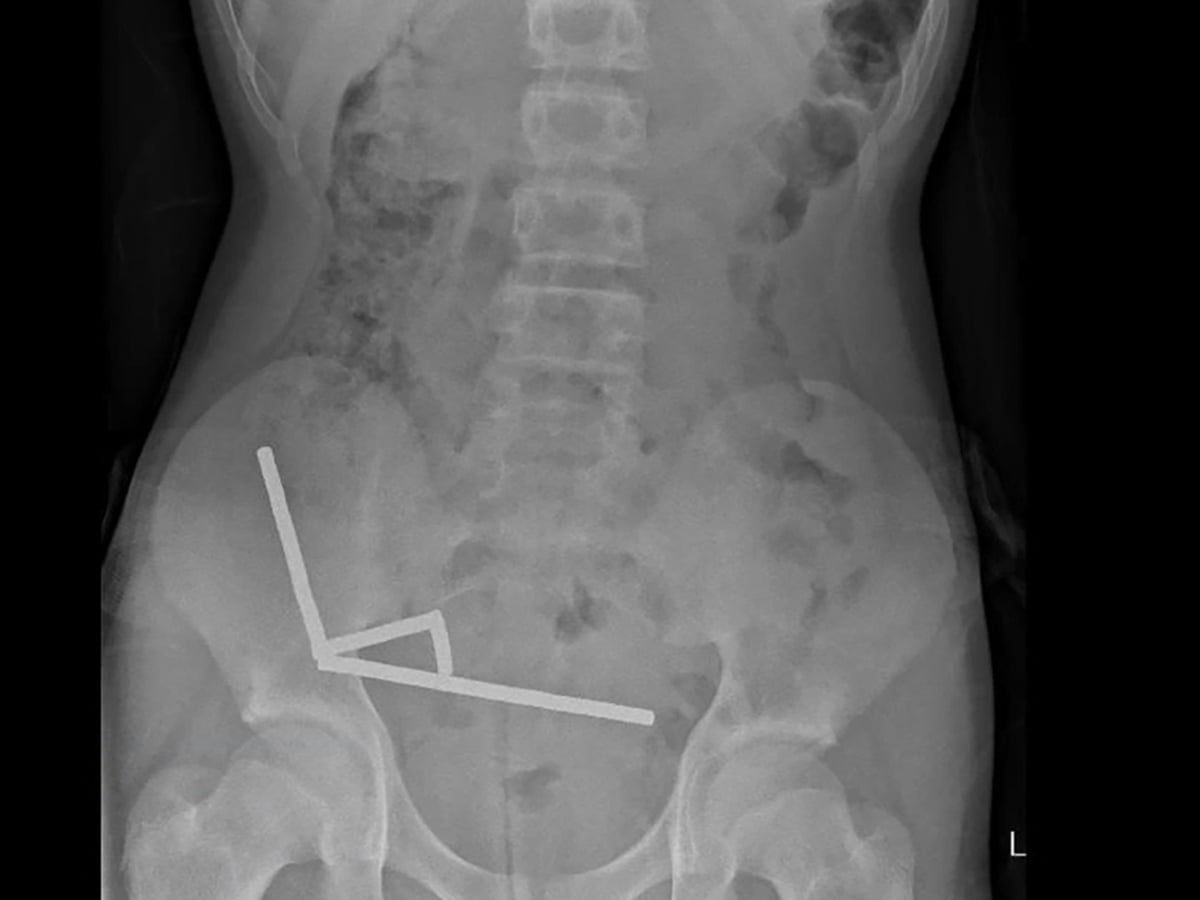

เหตุการณ์ดังกล่าวถูกเปิดเผยโดยสื่อท้องถิ่นในนิวซีแลนด์ และได้รับการยืนยันจากศัลยแพทย์ผู้ทำการรักษา (ซึ่งมักจะไม่เปิดเผยชื่อผู้ป่วยเด็กตามหลักจรรยาบรรณ) เด็กคนดังกล่าวถูกนำตัวส่งโรงพยาบาลด้วยอาการปวดท้องอย่างรุนแรง หลังจากการวินิจฉัยและเอกซเรย์ ทีมแพทย์ต้องตกตะลึงเมื่อพบกลุ่มก้อนของวัตถุแปลกปลอมจำนวนมากในระบบทางเดินอาหาร

การผ่าตัดฉุกเฉินเผยให้เห็นว่าวัตถุเหล่านั้นคือลูกปัดแม่เหล็กแรงสูง (High-Powered Magnets) หรือที่มักเรียกกันว่า “Buckyballs” จำนวนมากกว่า 100 ชิ้น

การที่ต้องนำแม่เหล็กมากถึง 100 ชิ้น ออกมา ถือเป็นกรณีที่รุนแรงอย่างยิ่ง สะท้อนถึงอันตรายมหาศาลของผลิตภัณฑ์ที่ถูกขายเป็น “ของเล่น” ชิ้นนี้